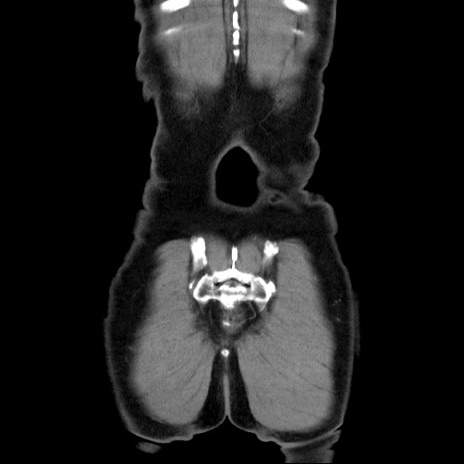

矢状断像